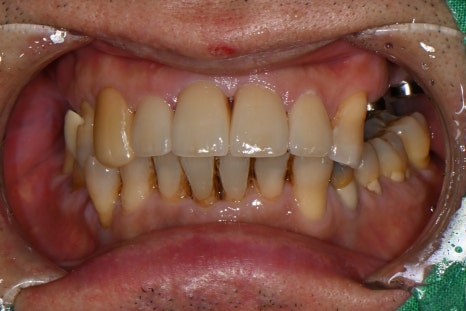

넘어지며 입술이 깊게 찢어지고, 앞니가 부러져 흔들리는 외상을 입으신 상황이었습니다.

입술 외측 6cm, 내측 4cm 관통 파열

윗 앞니 다수 탈구 및 흔들림

즉시 치아 재위치 후, 레진-와이어 스플린트로 고정

외상 직후 찢어진 입술 / 앞니 탈구 고정한 초기 응급처치 사진